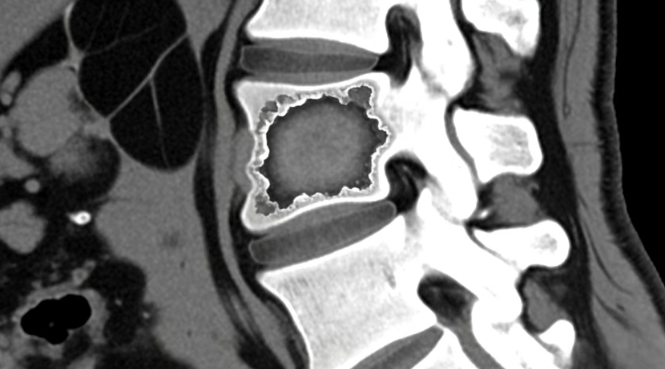

全腹增强CT检查揭示两项关键发现:腰3、4椎体骨质被破坏,右侧腰大肌形成巨大脓肿。结合影像结果及临床症状,医生最终确诊为腰椎结核——结核菌破坏脊柱后,沿肌肉间隙蔓延形成“冷脓肿”,波及阑尾区域引发类似阑尾炎的腹痛。超声率先捕捉脓肿线索,增强CT精准锁定脊柱病灶,二者协同让隐匿病灶无所遁形。